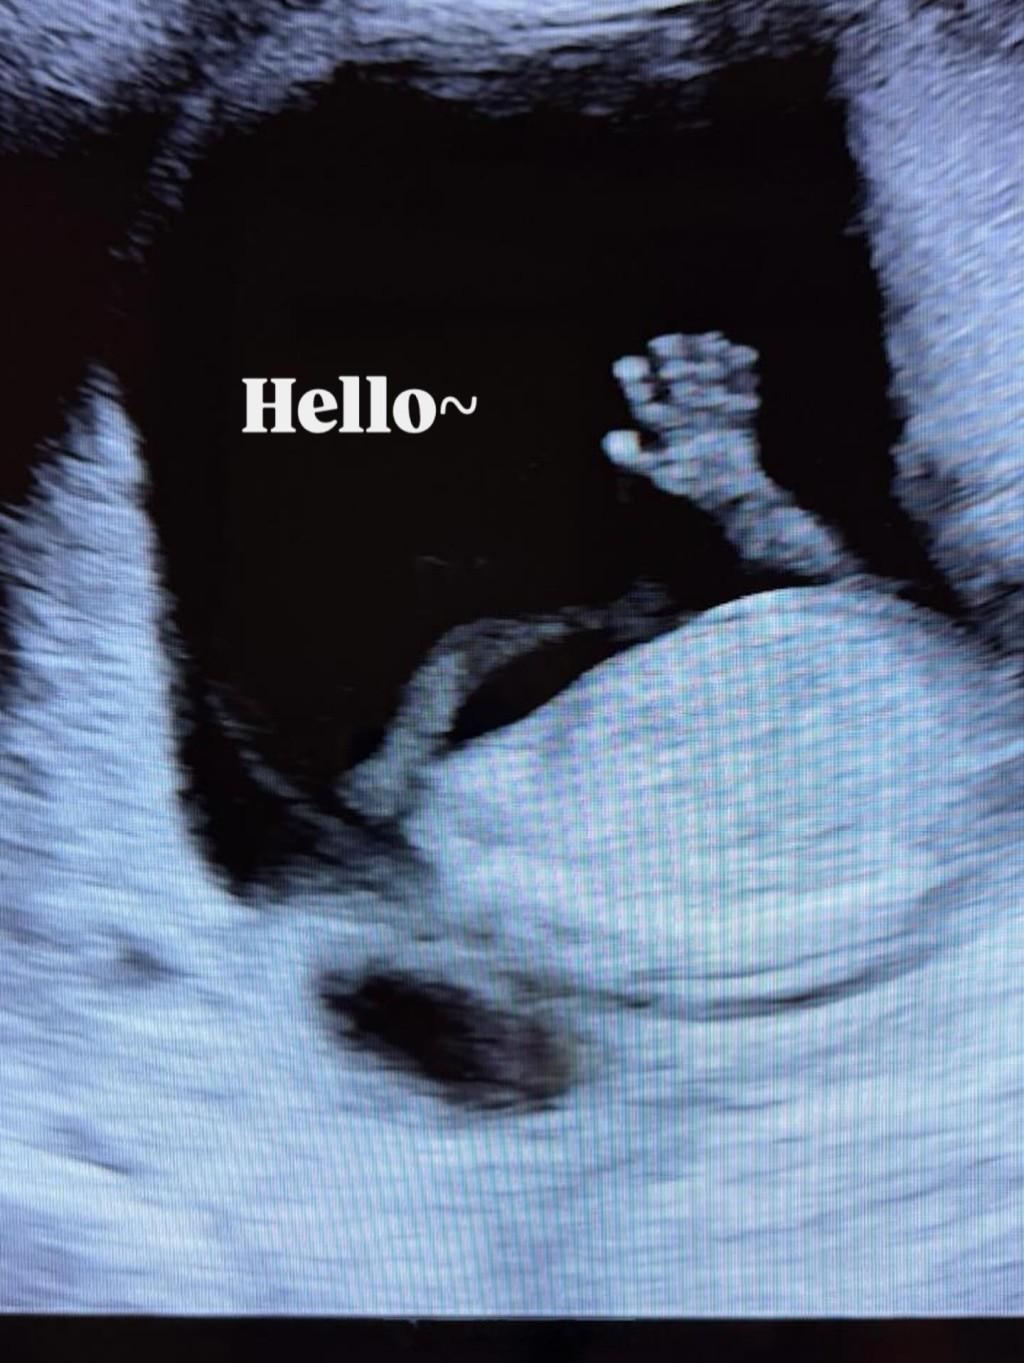

容天佑太太得天独厚手脚依然纤幼容天佑曾表示与太太Winnie都喜欢小朋友,希望生2个,笑言相信自己不是虎爸,只希望儿女开心成长。想不到二人新婚不足三个月,容天佑今日(30日)宣布太太Winnie怀孕,他贴上超声波的照片并说:“Coming soon...今年新年终于不用被三姑六婆问到哑口无言了。”已“见肚”的Winnie得天独厚,手脚依然纤幼,目测最少怀孕五个月或以上。

容天佑太太筹办婚礼2个月发现有孕相中所见,准爸爸容天佑很兴奋,一时亲太太的孕肚,一时又扮听BB的心跳,拿着超声波照片的神情,已经流露一脸慈父样,公开喜讯后,不少人留言恭喜,当中包括《爱回家》“李莫愁”张诗欣、前港男萧家浩、阮浩棕,更有好友留言:“难怪突然结婚!”容天佑大方地说:“都等了8年啦!”对于新婚未够3个月便就有喜,容天佑今日回复传媒表示是一个缘分:“开始筹办婚礼2个月左右,就发现有了,所以将婚礼的时间即刻缩短,所以一切都是上天的安排,是上天的礼物。”